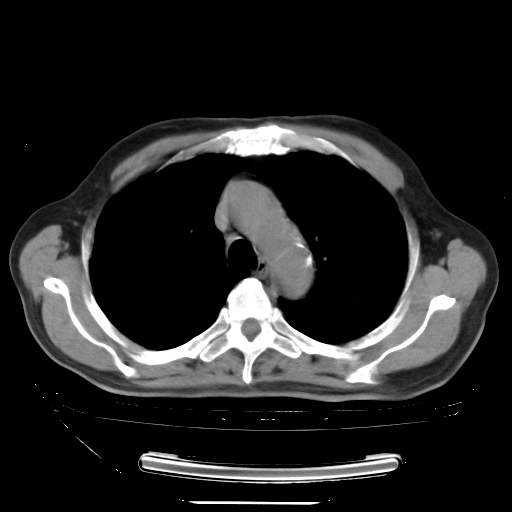

今天复查肺部CT,发现双肺广泛磨玻璃样改变。所以我把3月19日和5月9日相隔50天的肺部CT上传。请大家会诊。

2009年3月19日肺部CT片。

5月9日肺部CT(在4月27日齐鲁医院肺部CT描述部分肺组织磨玻璃样改变,12天后肺组织广泛磨玻璃样改变)